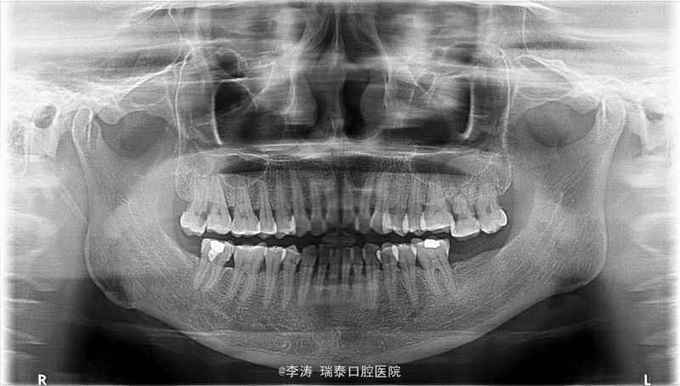

左上后牙自发痛一周

27牙伸长,松-,冷++,叩+-,近中邻面大面积龋坏,探及穿髓孔,x线片近中大面积龋坏近髓腔

27牙牙髓炎,行根管治疗 27磨短,测根长腭根11mm,近颊及远颊根15mm。置橡皮障,根管预备,根管消毒,根管充填。